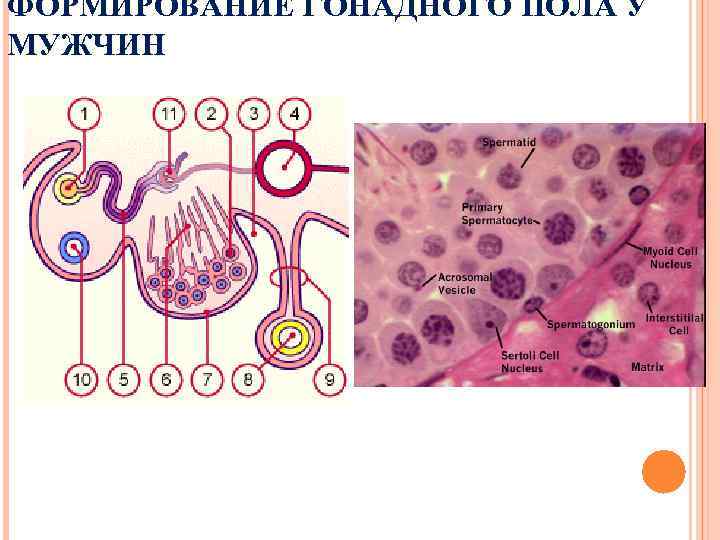

ФОРМИРОВАНИЕ ГОНАДНОГО ПОЛА У МУЖЧИН

ФОРМИРОВАНИЕ ГОНАДНОГО ПОЛА У МУЖЧИН